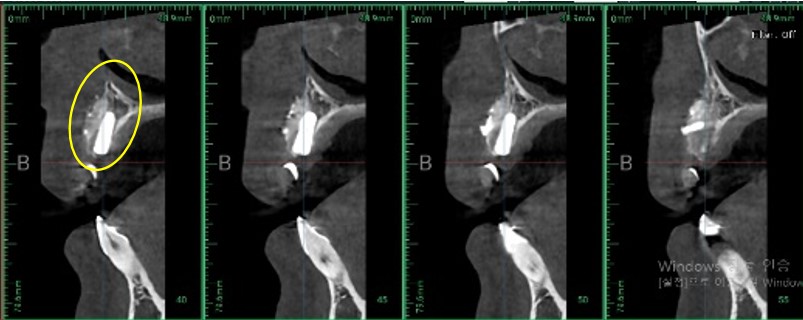

▲ 뼈 이식 완료 CT 사진

뼈이식 완료 후 임플란트 픽스쳐를 심은 상태입니다.

픽스쳐는 치아의 뿌리라고 생각해 주시면 되는데요. 제일 기초 공사인 기초가 불완전하게 되면

추후에 임플란트에 문제가 발생할 수 있습니다.

뼈이식을 하고 잇몸뼈가 완전히 생성될 때까지 4개월 정도 소요되었습니다.